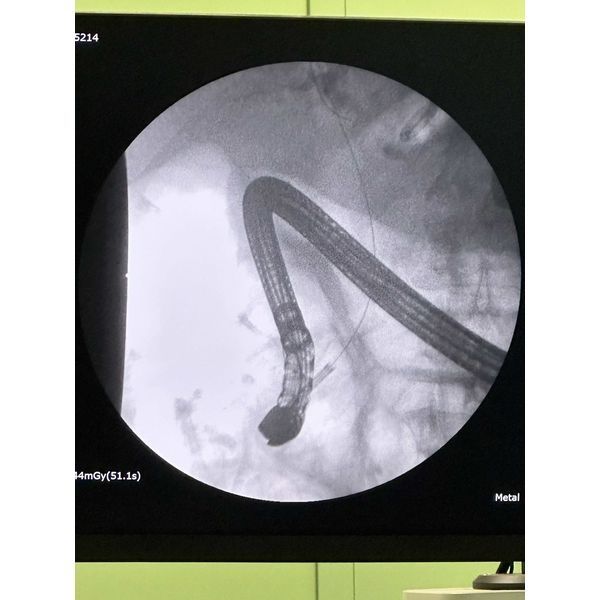

- ретроградную панкреатохолангиографию — комплексное исследование желчных протоков и протоков поджелудочной железы с помощью эндоскопа;

- папиллотомию — расширение выходного отверстия Фатерова сосочка для улучшения оттока желчи из общего желчного протока;

- холедохолитоэкстракцию — извлечение камней.

Однако извлечь крупные камни из общего желчного протока не удалось, поэтому через месяц пациент прошёл ещё одну операцию — наноимпульсное дробление камней (холедохолитотрипсию) с помощью аппарата SpyGlass.